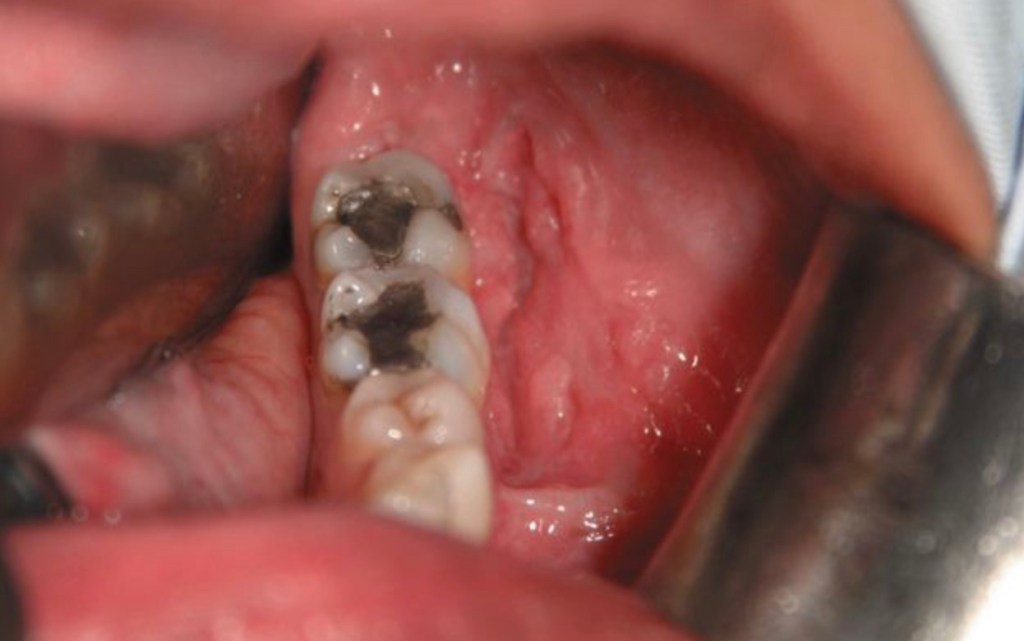

- Buccal carcinoma may be described as:

- Verrucous, exophytic or ulceroinfiltrative in character

- Patients who chew betel often have areas of:

- Erythroleukoplakia of the buccal mucosa or submucous fibrosis and consequent trismus:

- Making the detection of invasive squamous cell carcinoma difficult